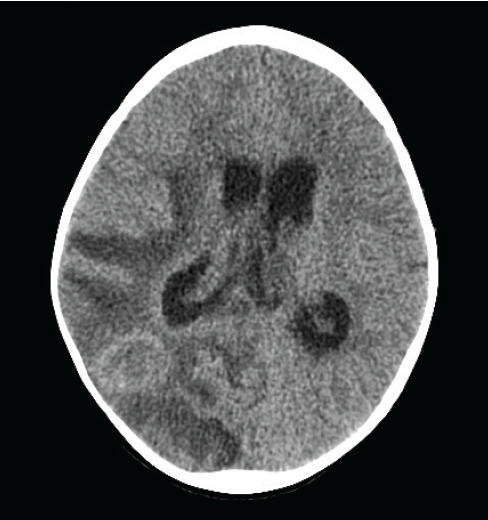

Jasmin Ahmed, BS, MS, MD; Franck Papillon, MD; Rolando Branly, MBBS; Ayman M. Salah, PhD; Syed A.A. Rizvi, PhD, MBA; Sultan S. Ahmed, MD

A 57-year-old man presented with an insidious onset of balance difficulties, including dizziness and vertigo, for some time.